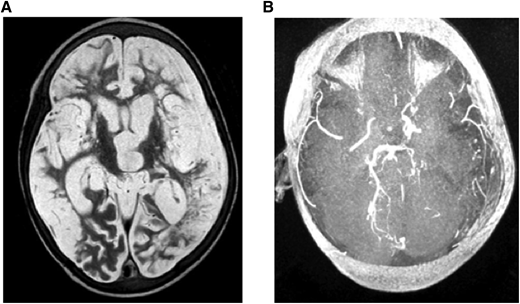

Figure 4.

(A) MRI: T2W (axial) and (B) MRA. Brain images from a 7-year-old quadriplegic boy showing (A) global cerebral infarction and (B) occlusion of both terminal internal carotid arteries and small left posterior cerebral artery but no moyamoya collaterals.

The presence of SCI or stenosis in patients with SCA was identified using MRI techniques on a Philips 1.5 Tesla scanner, including T2-weighted (T2W) MRI, fluid attenuated inversion recovery (FLAIR), and MRA. Representative images are shown in Figures 2 and 3 for 2 sample patients.